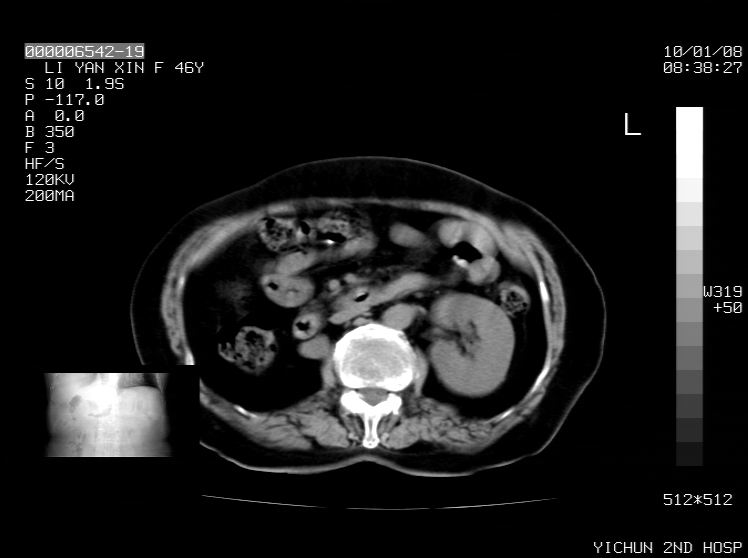

标题: CT24039:请会诊,女70岁,彩超考虑胆囊结石 [打印本页]

标题: CT24039:请会诊,女70岁,彩超考虑胆囊结石

右侧膈膨升,胆囊壁厚,右侧肾脏缺如。病史?

右侧膈膨升,右肾脏切除术后

右侧膈膨升,肝内钙化灶,胆囊壁厚,右侧肾脏缺如。病史?

右膈膨出,肝脏变异,肝内钙化,右肾缺如,脾大。

右侧膈膨升,肝内胆管结石?

右侧肾脏缺如。病史?

右侧膈膨升,胆囊壁厚,右侧肾脏缺如,增强,腔静脉旁是否是移位肾

肝脏变异致膈升高,肝左叶肝内胆管结石.右肾萎缩,左肾代偿肥大.

胆囊ct未见确切异常,请结合b超。右侧肾窝未见确切肾脏影,右肾萎缩?异位?

右侧膈膨升,肝内钙化灶,胆囊壁厚,右肾萎缩或发育不良。